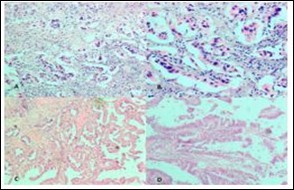

Figure 1.Photomicrographs showing A, Rokitansky agghste sinuses characteristic of chronic cholecystitis; B, Acute on Chronic Cholecystitis; C, Follicular Cholecystitis; D, Foamy macrophages admixed with mcaumulaig inflammatory infiltrate seen in Zbanikagmapincitma Cholecystitis (H&E)

Photomicrographs showing A, Rokitansky agghste sinuses characteristic of chronic cholecystitis; B, Acute on Chronic Cholecystitis; C, Follicular Cholecystitis; D, Foamy macrophages admixed with mcaumulaig          inflammatory infiltrate seen in Zbanikagmapincitma         Cholecystitis (H&E)